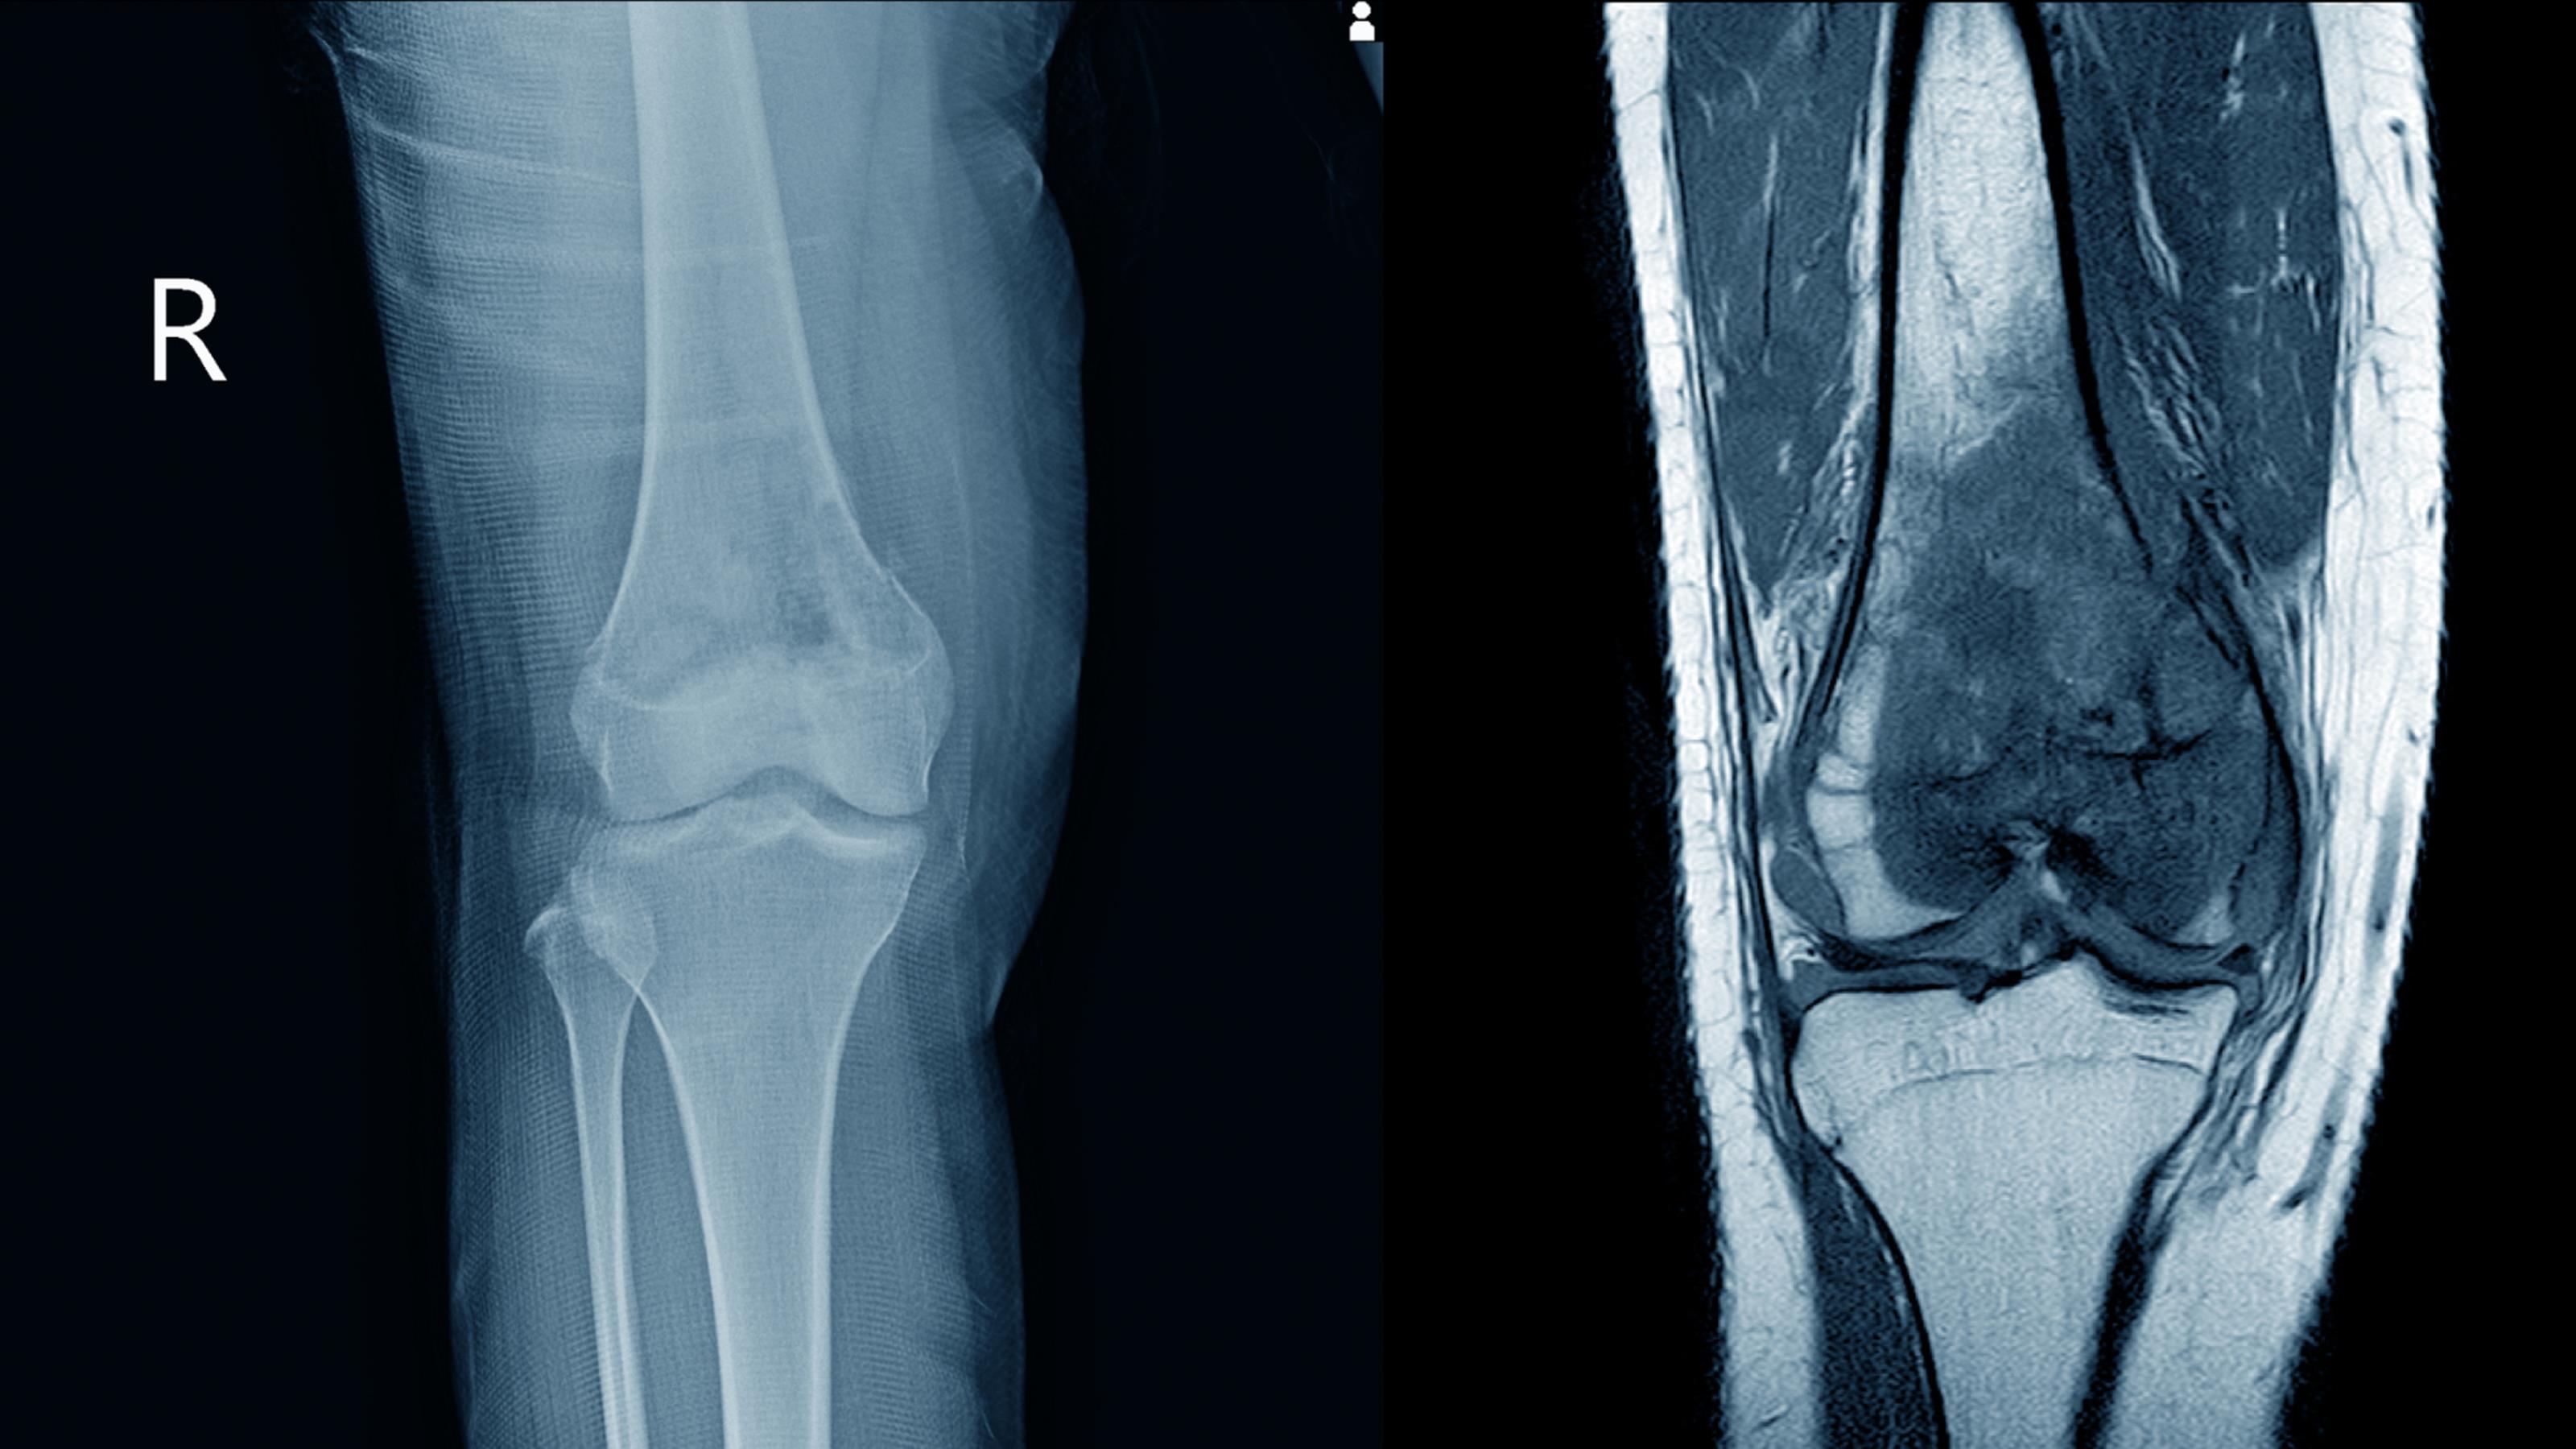

La ortopedia y traumatología es una rama de la medicina que se encarga del estudio de los problemas músculo esqueléticos, tanto en crecimiento y desarrollo así como consecuencias del desgaste progresivo de la edad. Los accidentes pueden generar lesiones óseas y musculares que requieren de atención urgente. oportuna y llegan a condicionar secuelas irreversibles. Contamos con experiencia enfocada a el dolor de "rodillas", ya sea por desgaste o en lesiones deportivas. Tenemos convenio con aseguradoras y nos adaptamos a tabuladores de las mismas sin cobros adicionales.